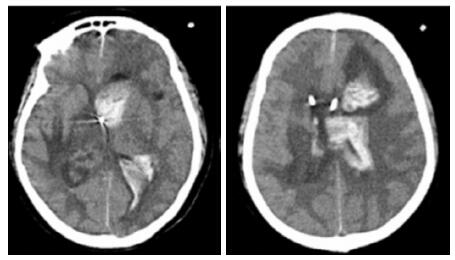

转入ICU后呼吸机辅助通气、甘露醇100 mL/8 h静滴脱水、头孢呋辛1.5 g/12 h静滴抗感染,肠内营养等支持治疗。当晚血常规:白细胞13.3×109/L,中性粒细胞百分比85.3%,C反应蛋白17.1 mg/L,降钙素原0.64 ng/mL。脑室外引流术后次日血化验:白细胞16.6×109/L,中性粒细胞百分比92.8%,C反应蛋白78.4 mg/L;从脑室外引流管留取脑脊液检验:有核细胞6×106/L,红细胞1 960×106/L,蛋白含量1.717 g/L,葡萄糖4.72 mmol/L,细菌培养阴性,涂片未找到细菌;复查头颅CT示:脑室扩张好转,右侧丘脑、左侧岛叶病变伴出血(图 2);胸部CT示,两肺间质性肺炎下叶为著,较前(2019年6月21日)部分好转(图 3)。考虑到炎症指标升高,遂改哌拉西林他唑巴坦3.375 g/12 h静滴抗感染。此后经脑室外引流管反复留取脑脊液送检涂片及培养均阴性。术后第5天行“导航下立体定向颅内病灶活检术+双侧omaya囊置入术”,术中穿刺液呈黄色黏稠脓性,考虑脑脓肿,留取脓液送高通量测序(next-generation sequencing, NGS),并升级为美罗培南2 g/8 h联合利奈唑胺0.6 g/12 h静滴抗感染治疗。术后第7天患者突发血压升高、瞳孔不等大,昏迷程度加深;急查头颅CT示,双侧脑室钻孔引流术后改变,双侧侧脑室引流管走形区出血伴血肿形成;右侧丘脑区积液、积血,双侧脑室积血新发(图 4),甘露醇加量至250 mL/8 h联合地塞米松5 mg/6 h静滴加强脱水;当日术中脓液高通量测序结果回报:皮疽诺卡菌(序列数52 867个)、支气管戈登菌(序列数10个)。确诊脑诺卡菌病,抗菌治疗方案改为亚胺培南西司他丁0.5 g/6 h静滴,联合利奈唑胺0.6 g/12 h和复方磺胺甲恶唑片(0.48 g/片)3片/6 h口服。此后患者仍伴低热,炎症指标呈上升趋势。术后2周患者再次突发血压升高、瞳孔不等大、对光反射消失、神志深昏迷,急查头颅CT示再发脑疝(图 5),急诊行“去骨瓣减压术+脑内血肿清除术”,术后患者仍呈深昏迷状态,双侧瞳孔散大、对光反射消失,次日自动出院。

| 双侧脑室钻孔引流术后改变,双侧侧脑室引流管走形区出血伴血肿形成;右侧丘脑区积液、积血,双侧脑室积血新发 图 4 患者2019-10-06头颅CT结果 |

| 双侧侧脑室引流管走形区出血伴血肿形成;右侧丘脑区积液、积血,脑室积血;左引流管旁血肿较前(2019-10-06)增大,脑室积血增多,中线右移。左岛叶及颞叶斑块状低密度影 图 5 患者2019-10-13头颅CT平扫结果 |